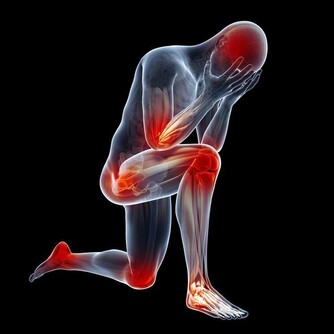

*****4.保護心腦快減大肚腩*****

很多中年男士以“將軍肚”為榮。這一肚子的油水,帶來的可是巨大的健康風險,比如高脂血症。

高脂血症一方面與攝入過多的脂類有關,另一方面與自身脂代謝功能異常有關。

過高的血脂對血管內皮會造成嚴重的損傷,形成斑塊,造成管腔的狹窄,並誘發其它疾病比如動脈粥樣硬化性心髒病等,同時,過高的血脂還可能會誘發急性胰腺炎。

各位大腹便便的男士為了自己深愛的家人,請減掉肚子,多做一些運動。